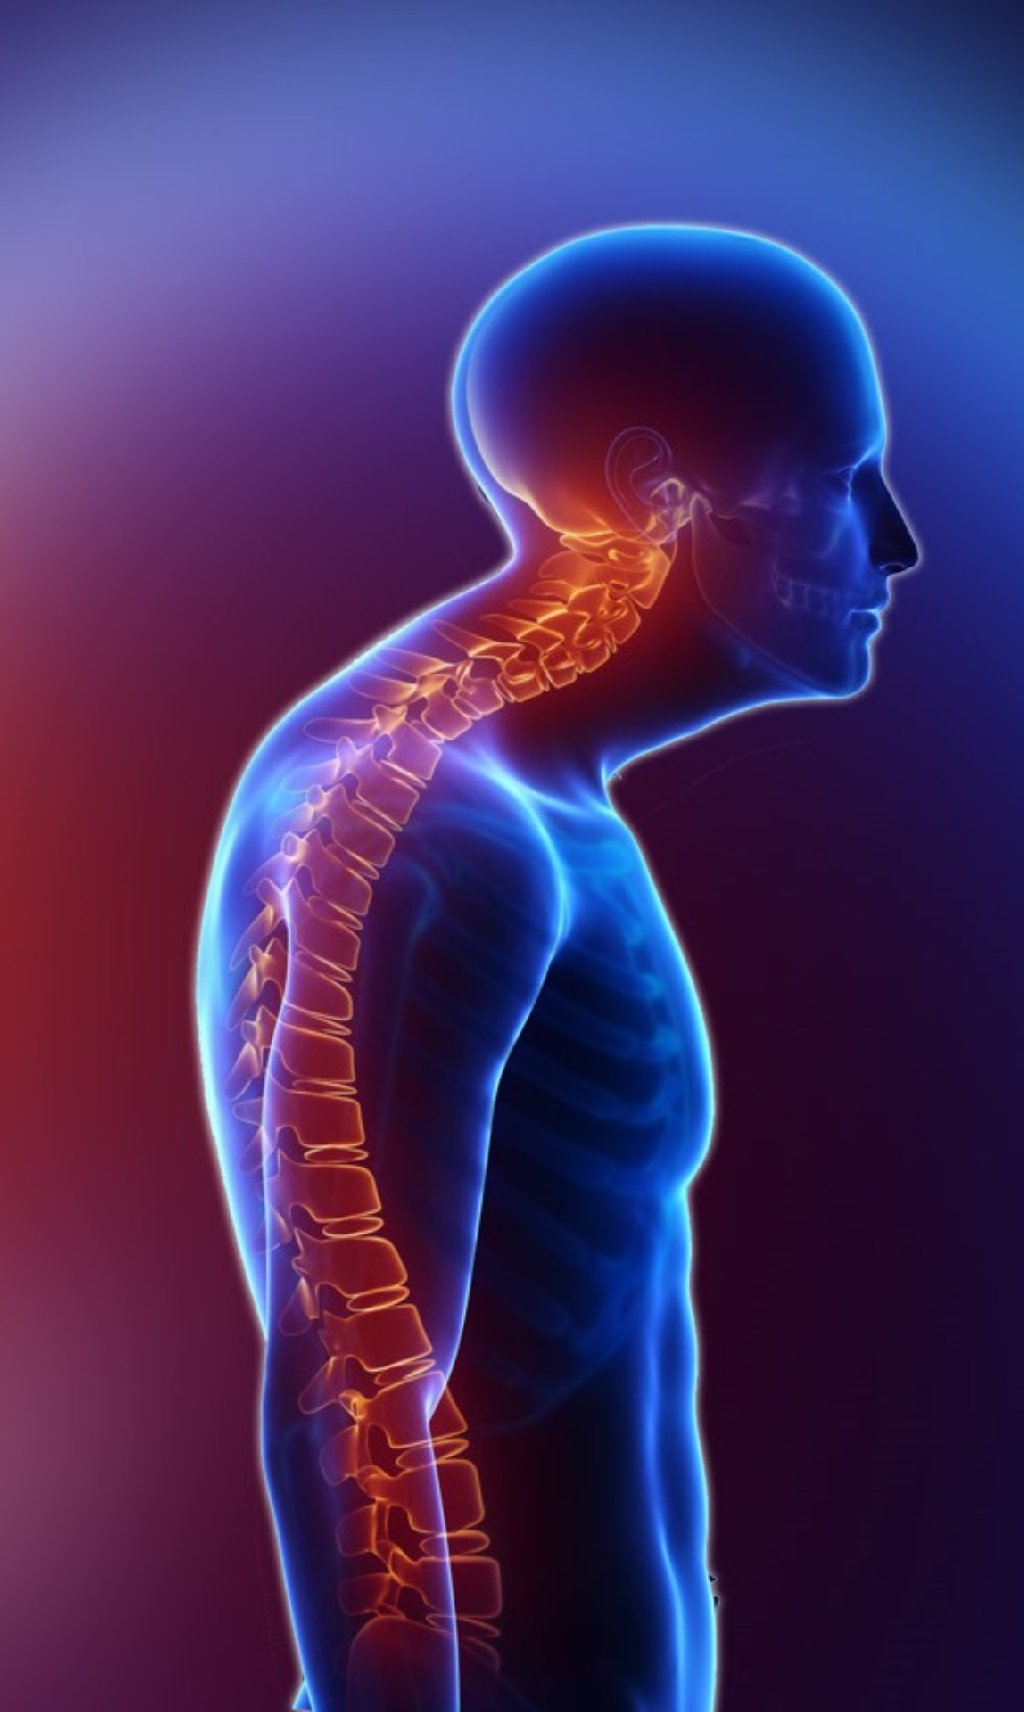

Kifozun səbəbləri və növləri ola bilər: Postural kifoz: Ən çox rast gəlinən növdür və adətən ...

Skoliozun nəticələri və səbəbləri müxtəlif olabilir: Nəticələr: Skolioz, ağrı və yorgunluq kim ...

Simptomlar: Kəsmə: Onurğa normaldan daha çox irəli əyilmiş kimi görünə bilər. Ağrı və Gərginlik: ...